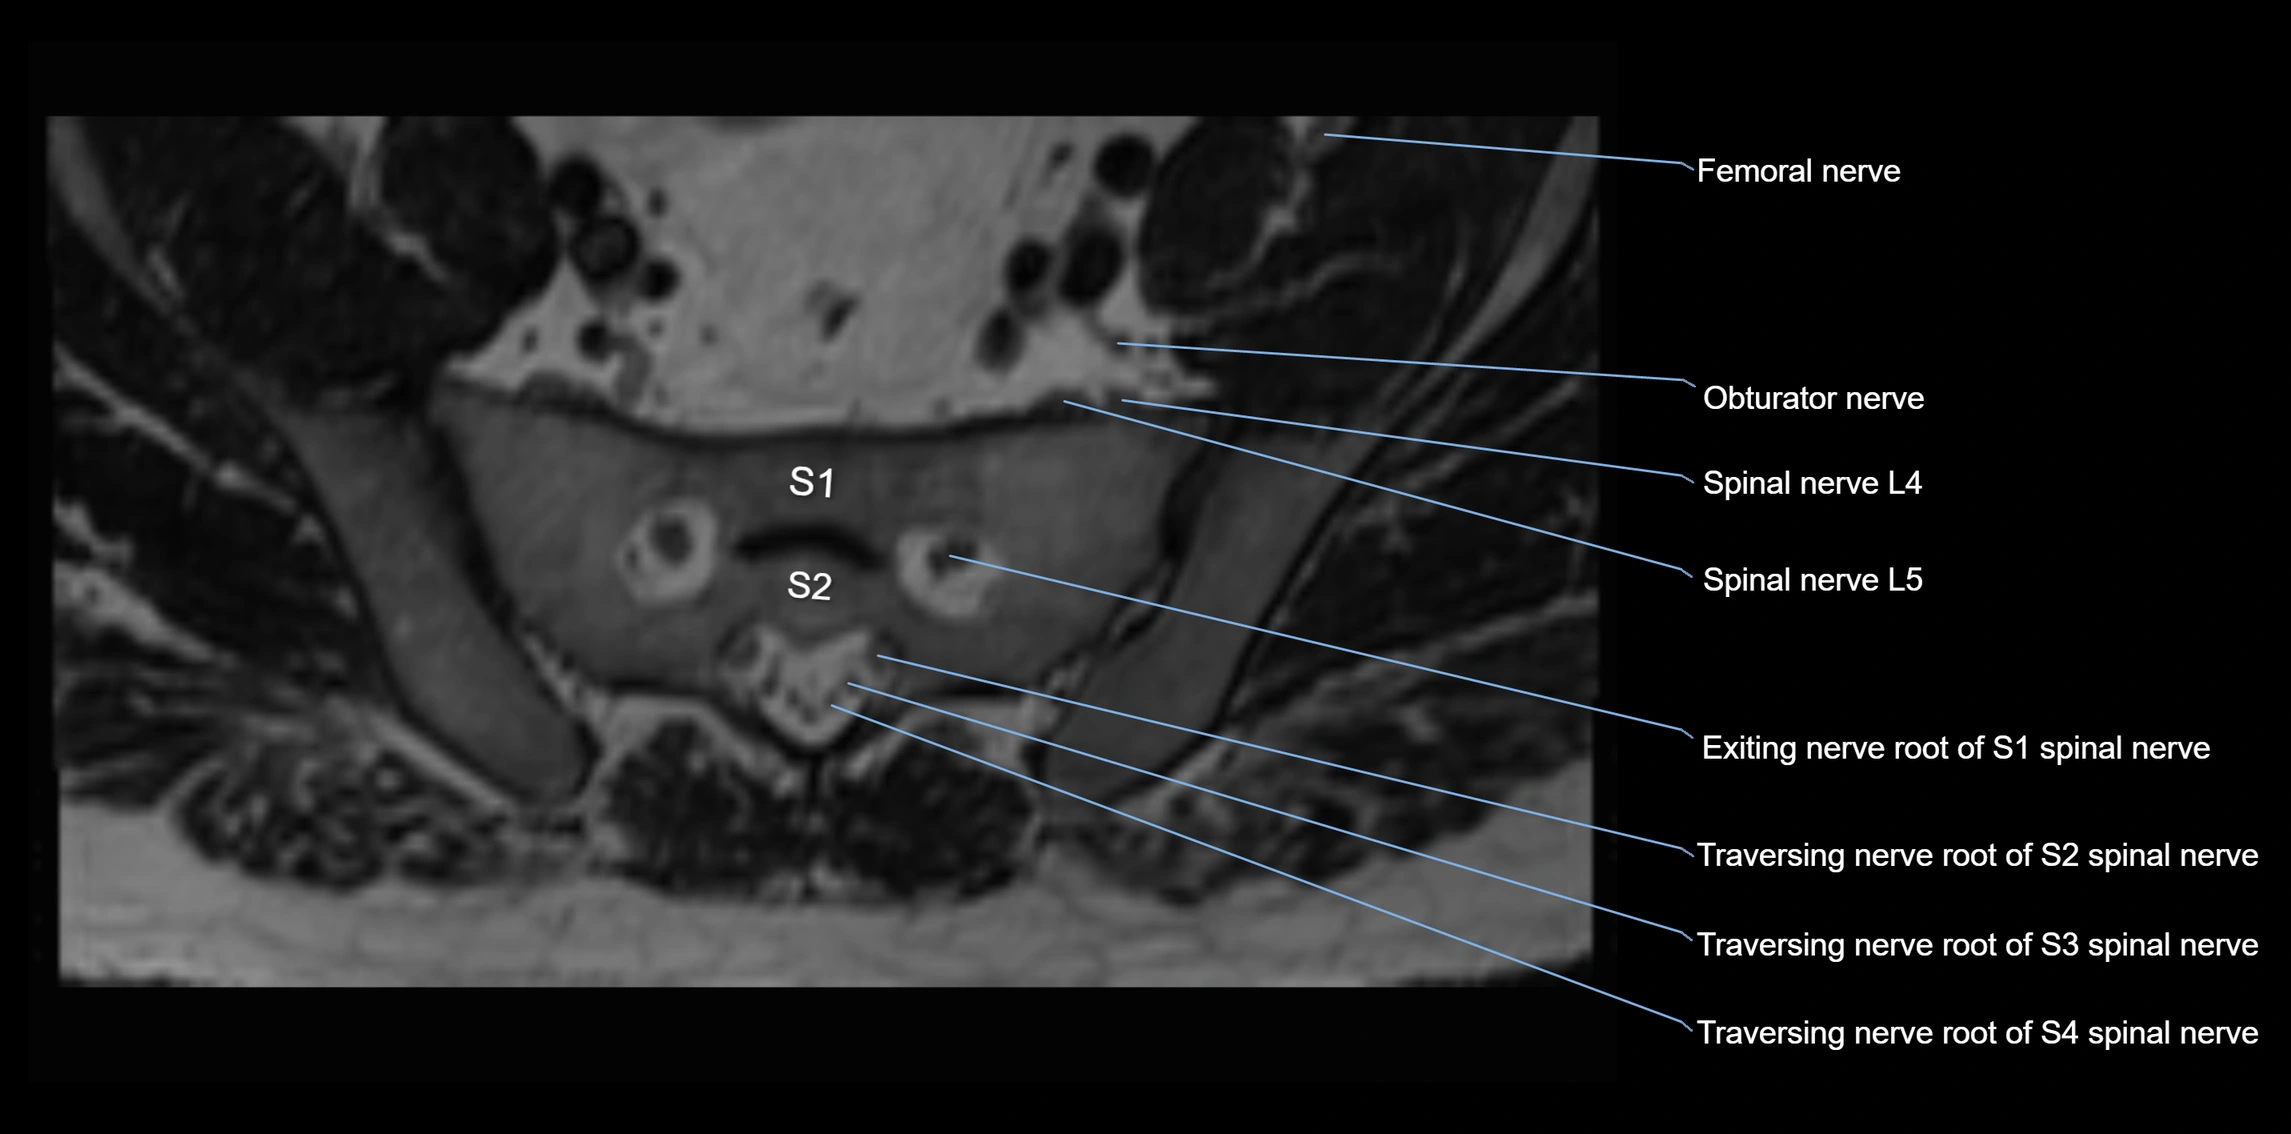

MRI image

image